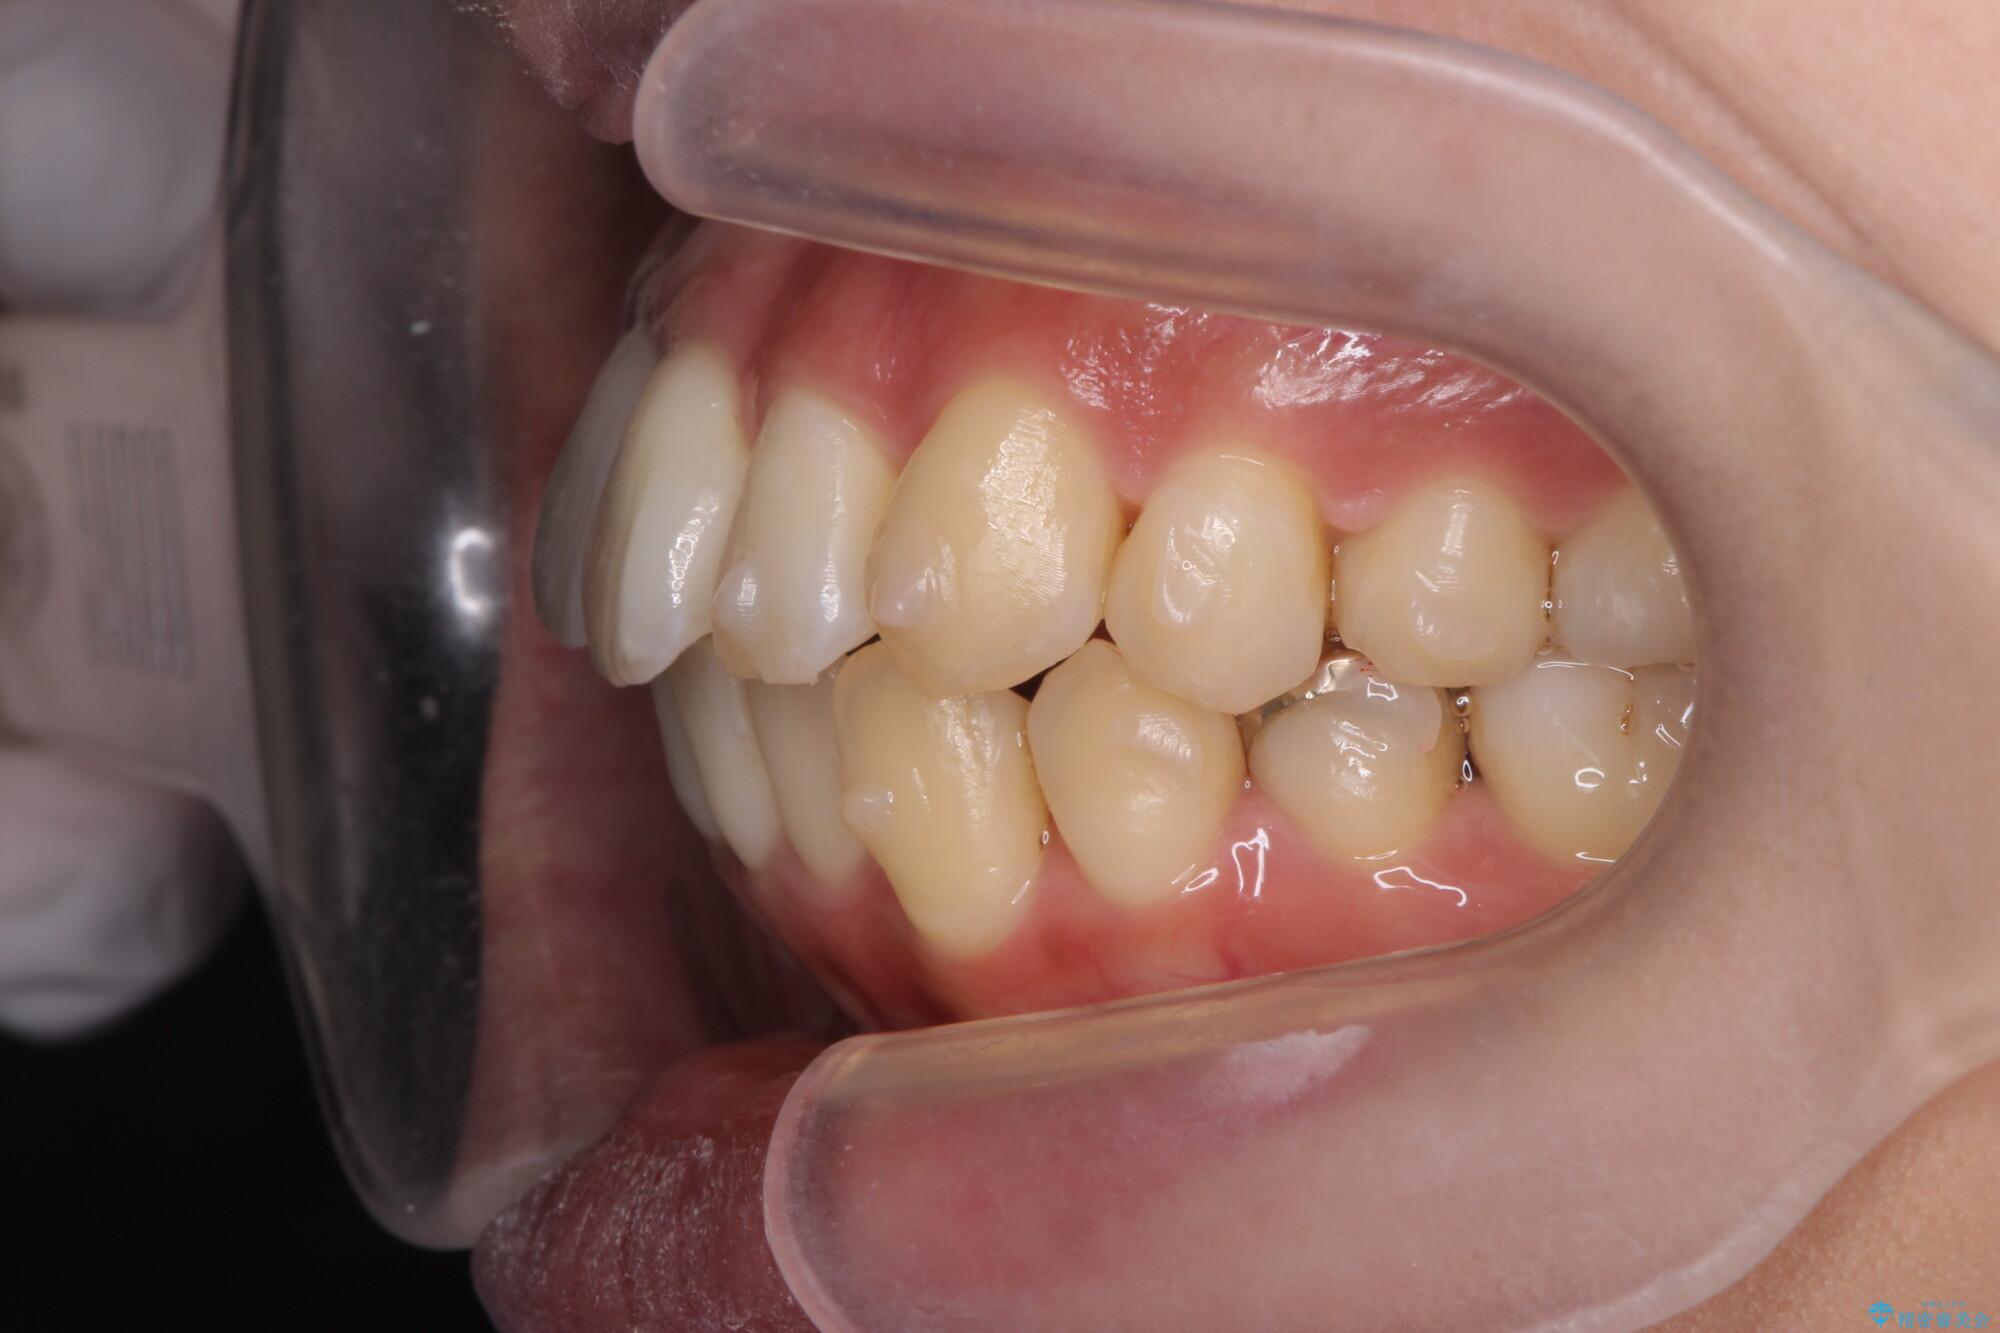

前歯のガタつきの改善を主訴にご来院されました。 特に犬歯の傾きが気になるとのことでした。

犬歯がかなり手前に傾いていましたが、ガタつきはそれほど強くないため非抜歯でマウスピース矯正が可能と判断しました。

治療前

気になる犬歯のガタつきをマウスピース矯正で改善 治療前画像 気になる犬歯のガタつきをマウスピース矯正で改善 治療前画像 気になる犬歯のガタつきをマウスピース矯正で改善 治療前画像 気になる犬歯のガタつきをマウスピース矯正で改善 治療前画像